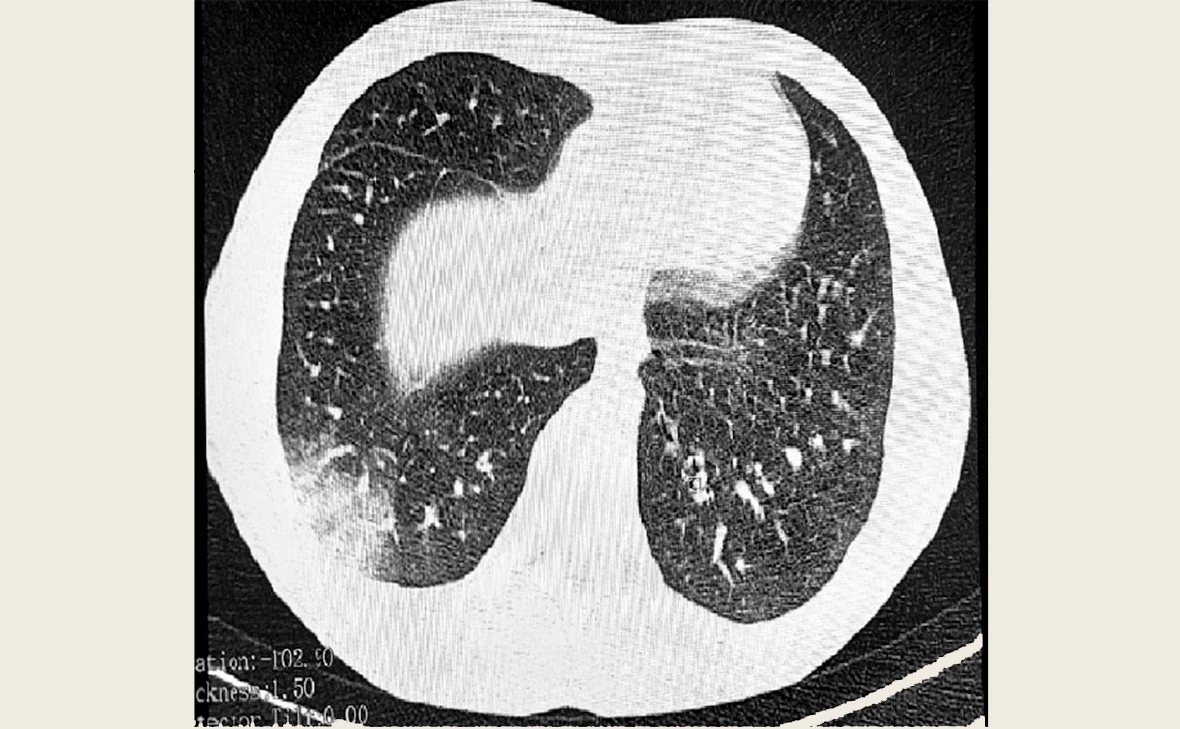

Фото: Управление Роспотребнадзора по Томской области

EVALI — это неинфекционное заболевание легких, которое появляется из-за курения электронных сигарет. Оно поражает бронхиолы и проявляется в виде их сужения, воспалений и рубцов на дыхательных органах. EVALI (E-cigarette or Vaping product use-Associated Lung Injury), или повреждение легких, ассоциированное с курением электронных сигарет и вейпов, прозвали «попкорновой болезнью» из-за схожести с заболеванием рабочих фабрик по производству попкорна — бронхиолитом облитерирующим. Один из симптомов, обнаруженных врачами, — треск в легких, который напоминает лопающийся попкорн.